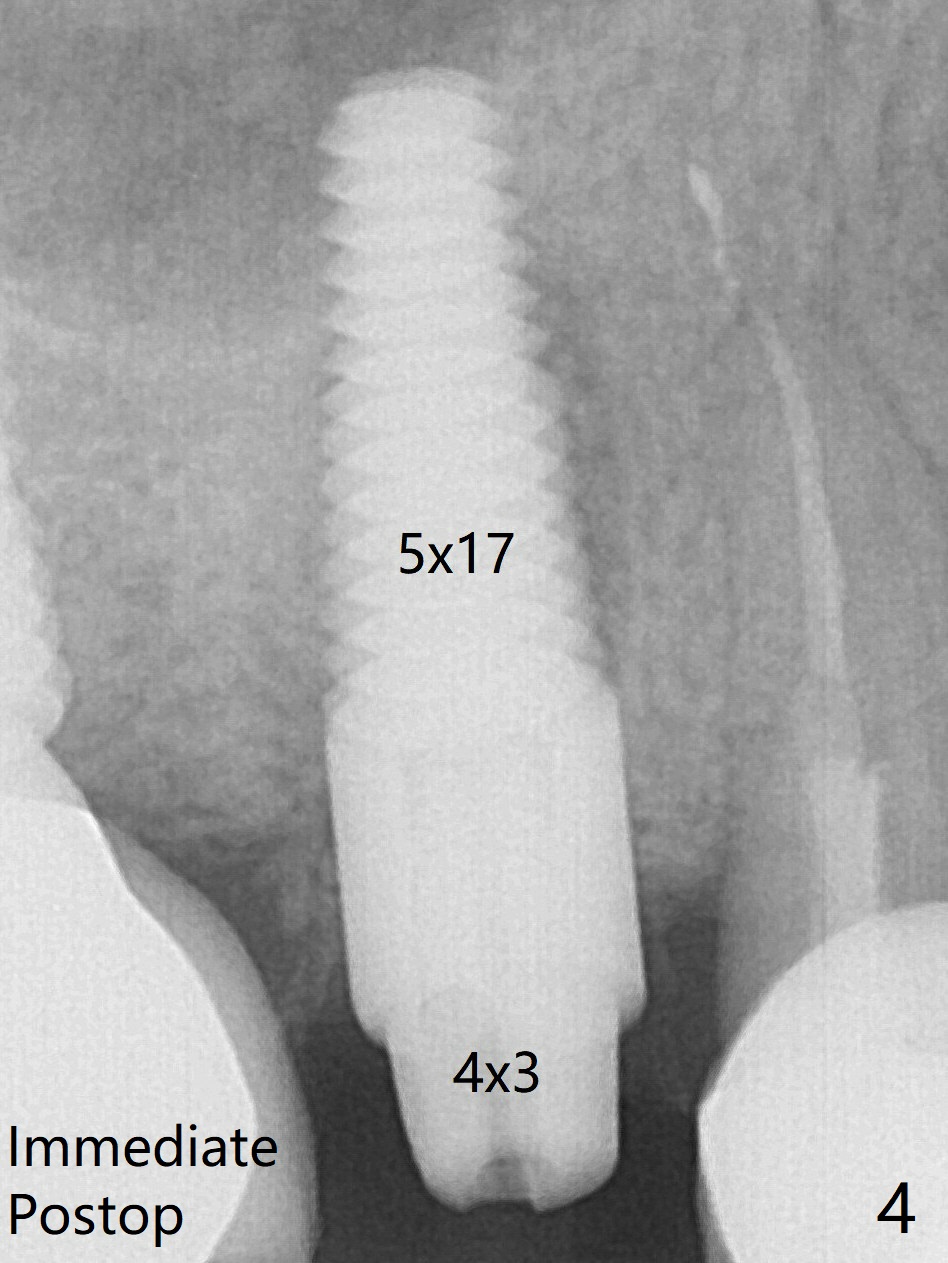

A 5x17 mm tissue level implant is placed with >45 Ncm; with immediate placement of a 4x3 mm abutment (Fig.4), an immediate provisional is fabricated.  There is no crestal bone resorption 6.5 months postop (Fig.7), while the periradicular radiolucency decreases.